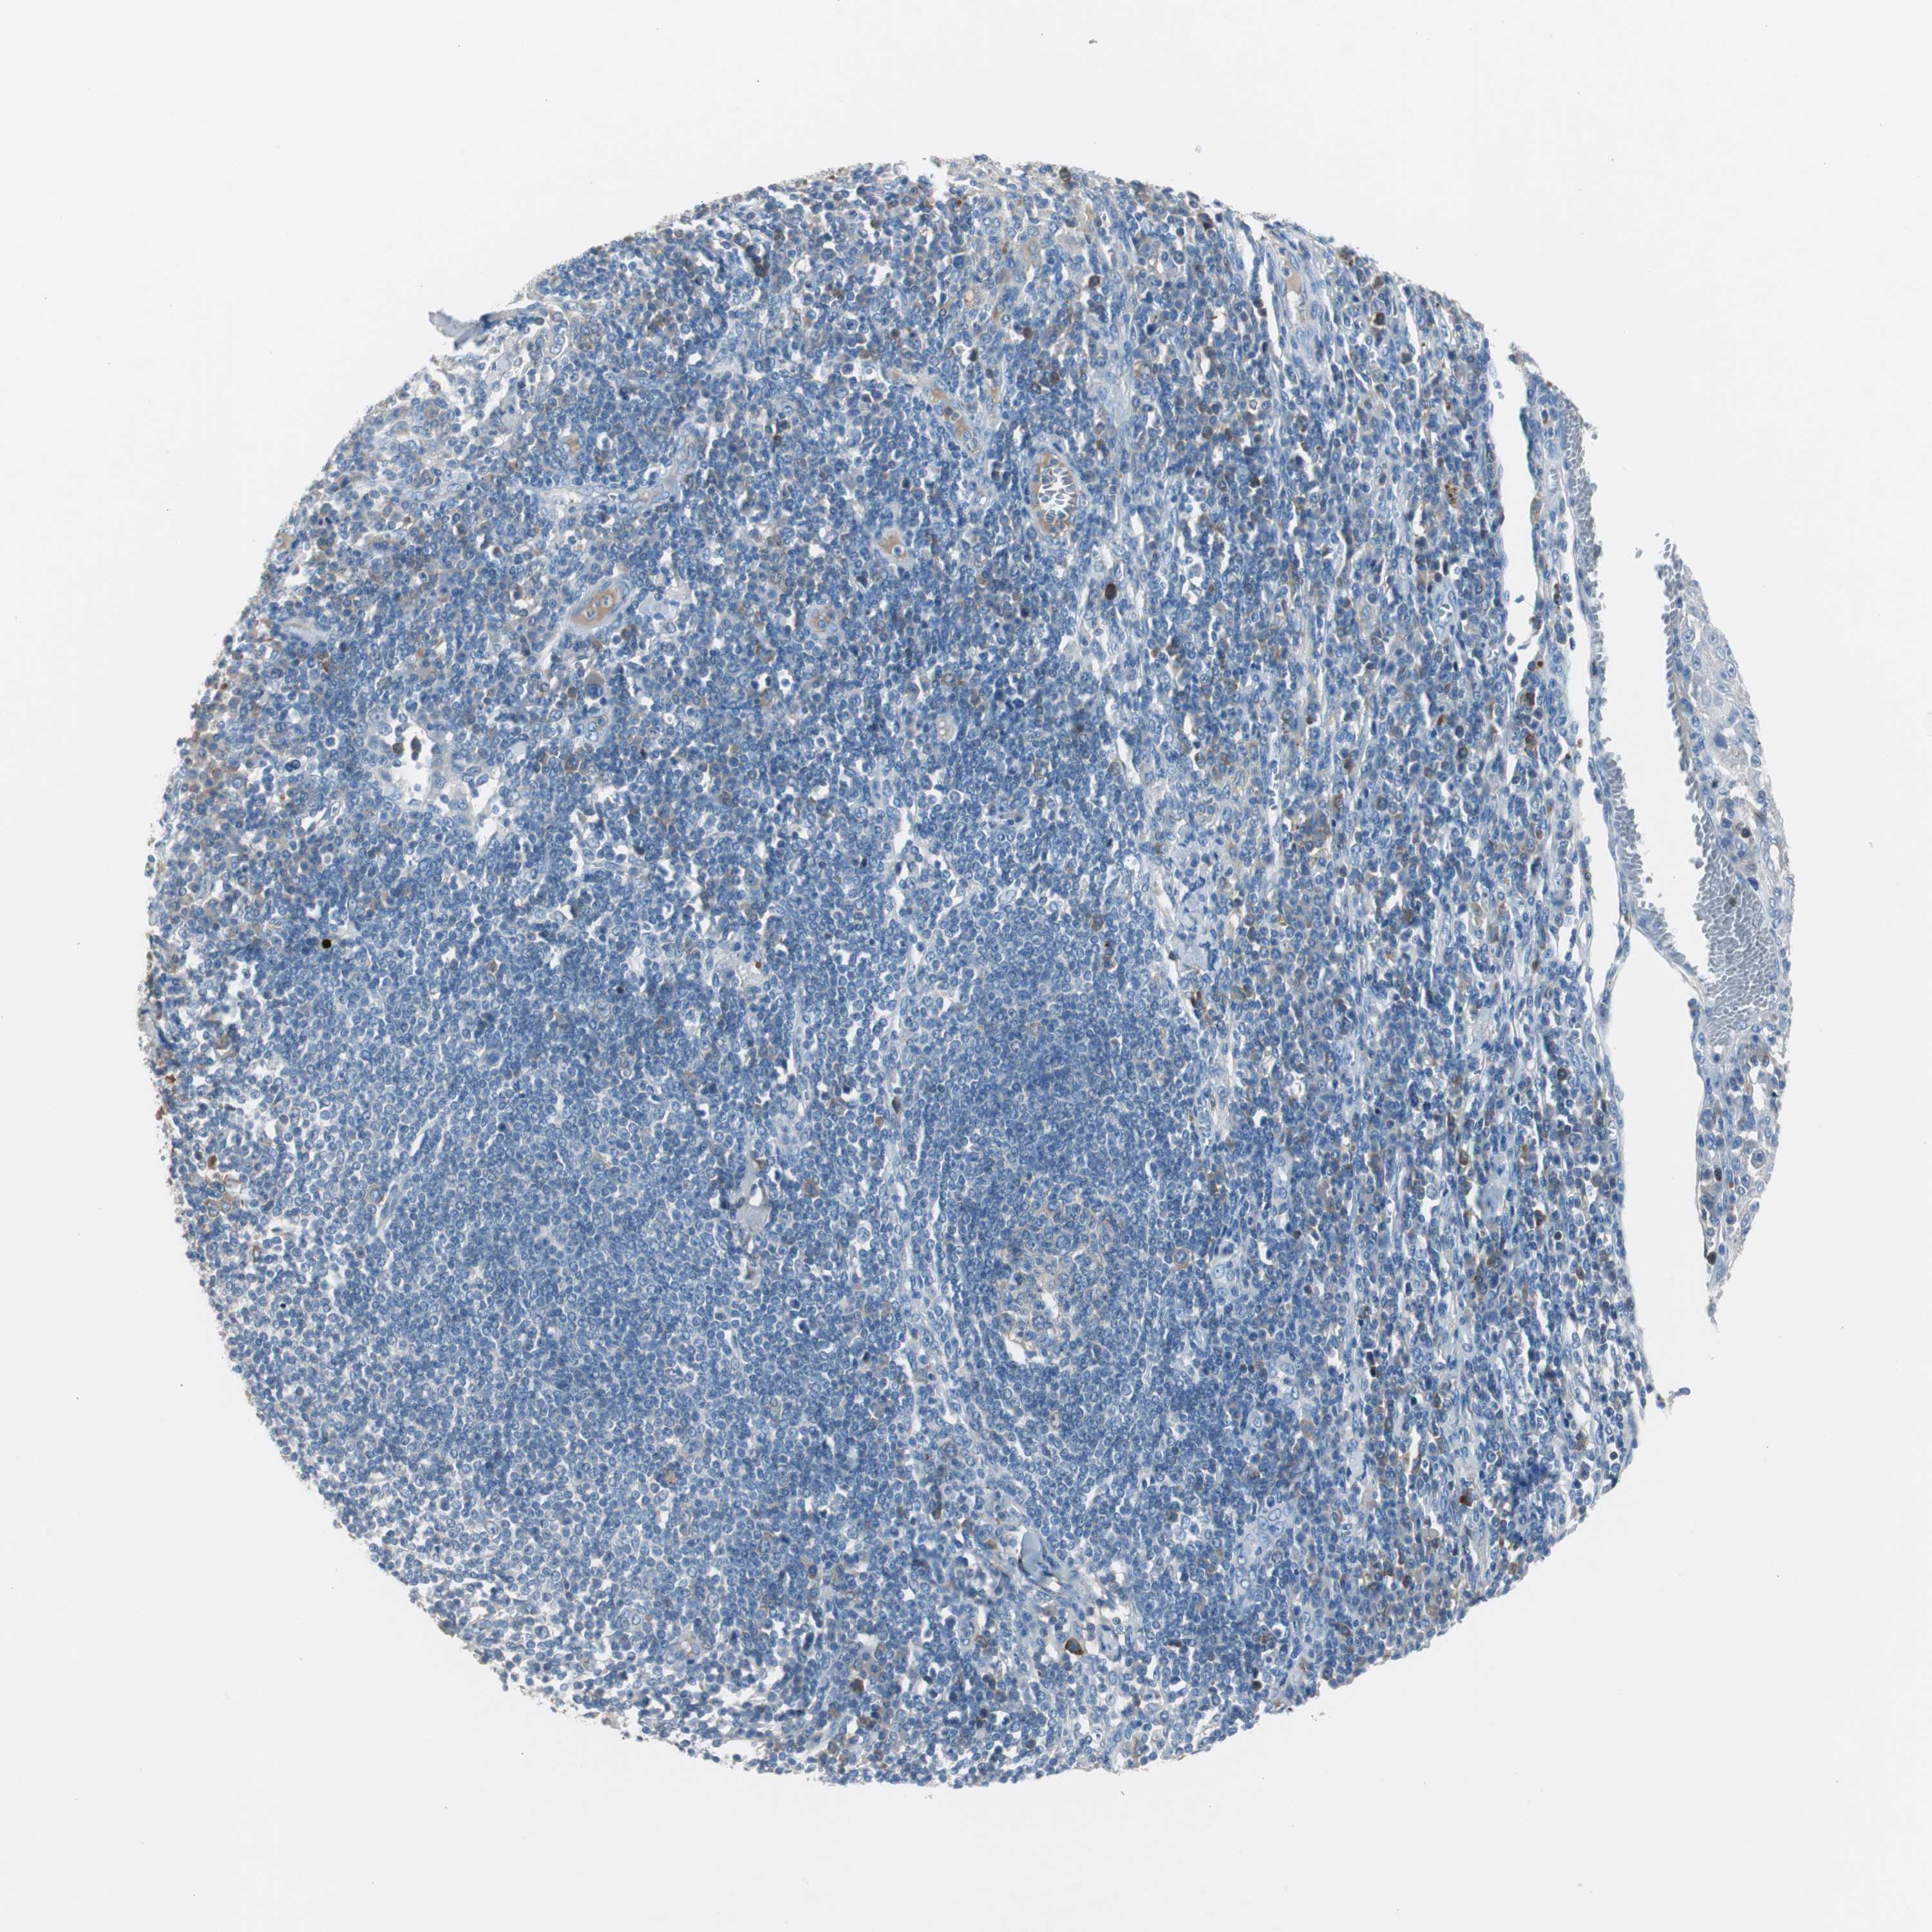

SKIN CANCER - Protein expressioni

A mouse-over function shows sample information and annotation data. Click on an image to view it in a full screen mode. Samples can be filtered based on level of antibody staining by selecting one or several of the following categories: high, medium, low and not detected. The assay and annotation is described here.

Antibody stainingi

Antibody staining in the annotated cell types in the current human tissue is reported as not detected, low, medium, or high, based on conventional immunohistochemistry profiling in selected tissues. This score is based on the combination of the staining intensity and fraction of stained cells.

Each image is clickable and will lead to virtual microscopy that enables deeper exploration of all samples and also displays staining intensity scores, fraction scores and subcellular localization as well as patient and tissue information for each sample.

Antibody HPA005825

Squamous cell carcinoma, NOS

Basal cell carcinoma